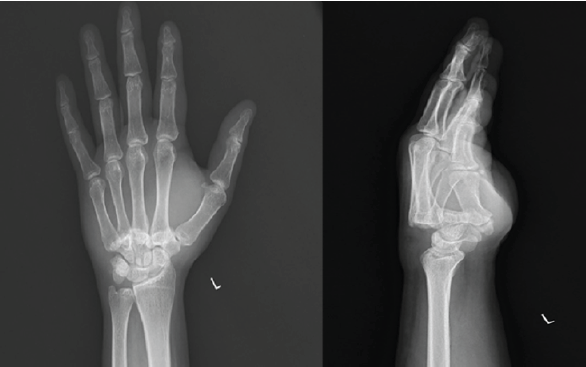

A 36-year-old manual laborer presented to a tertiary care hospital with gross swelling over the dorsum of the left hand following a fall from a scooter (Fig. 1).

Figure 1: Pre-operative radiographs showing dorsal dislocation of the 2nd–5th metacarpals. Overlapping of the metacarpals over the carpal bones with loss of parallelism and “M” lines seen over the posteroanterior radiograph.

He was managed with analgesics, a crepe bandage, and limb elevation initially for 2 days before reporting to the hospital. Plain radiographs of the left-hand anteroposterior and lateral views revealed dorsal CMC dislocations of all four fingers of the ulnar side of the left hand (Fig. 2). An oblique view of the left hand was taken to confirm the diagnosis. A 3D computed tomography (CT) scan was done to rule out fracture-dislocations (Fig. 3).